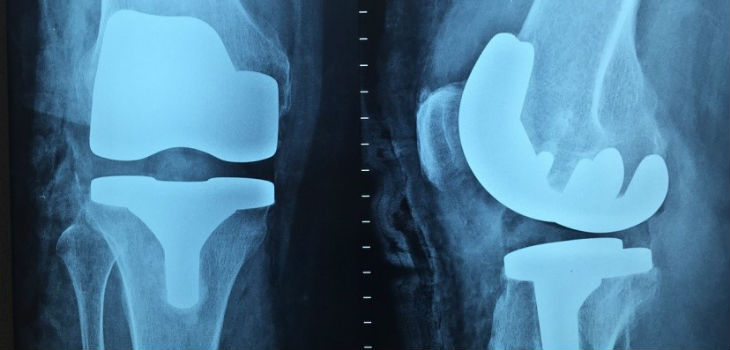

Los biomateriales metálicos son imprescindibles en prótesis que estén sometidas a esfuerzos elevados, tales como las prótesis de cadera y de rodilla. Sin embargo, incluso los metales empleados en medicina no generan una reacción óptima en el organismo. La respuesta natural del cuerpo hacia estos biomateriales metálicos tiende a recubrirlos por una especie de cicatriz, que aísla al material de los tejidos funcionales que lo rodean. Dicha cicatriz puede suponer un problema a corto plazo al favorecer la posibilidad de que aparezca una infección en el entorno de la prótesis y, además, a largo plazo puede inducir el aflojamiento del implante. Como solución a ambas situaciones suele ser necesario someter al paciente a una nueva intervención quirúrgica. Teniendo en cuenta todo esto, parece clara la conveniencia de conseguir establecer un contacto íntimo y fiable entre el material y el tejido funcional circundante. De esta manera se disminuiría la posibilidad del rechazo al implante aumentando su vida útil.

Proliferación de células madre mesenquimales sobre (A) aleación de titanio sin tratamiento, y (B) aleación de titanio sometida al tratamiento de biofuncionalización AVS. Fuente: UPM.